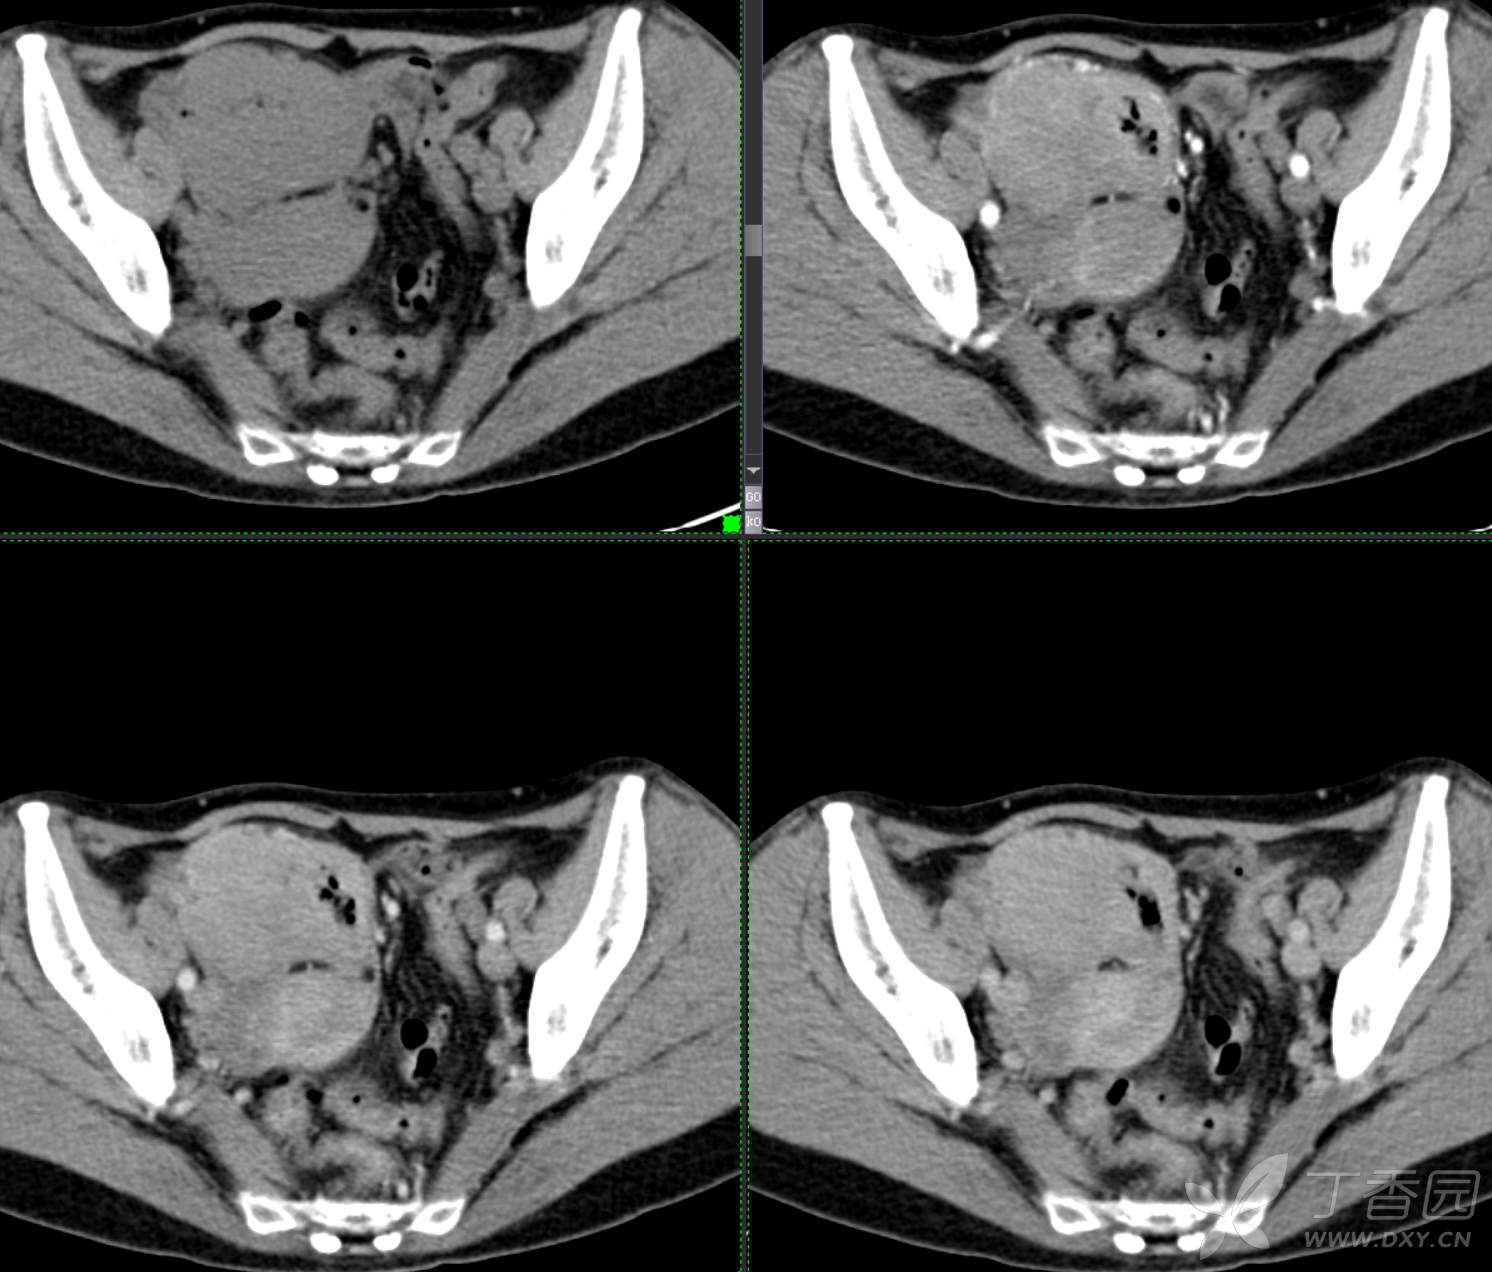

腹组13:患者,女,62岁,大便习惯改变2月余

主 诉: 【大便性状改变2月余】

现病史: 患者2月余前无明显诱因下出现大便次数增多,无明显血便黑便及粘液脓血便,大便次数由1次/日增加至2-3次/日,大便形状变细如小指,偶稀软不成形,无腹痛腹胀腹泻,无恶心呕吐、胸闷气促,肛门排气通畅,无发热盗汗。至当地医院就诊,行肠镜检查发现"回盲部占位"。为进一步治疗,我院门诊拟"回盲部肿瘤"收住入院。